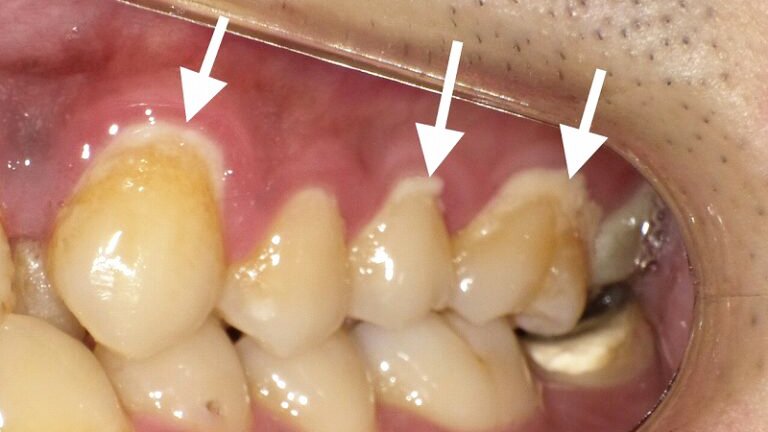

特定部位(歯頚部や奥歯)に偏って蓄積

放置されると毒性が高まり、歯ぐきを攻撃

強固なバイオフィルムとなり歯磨きでは除去困難